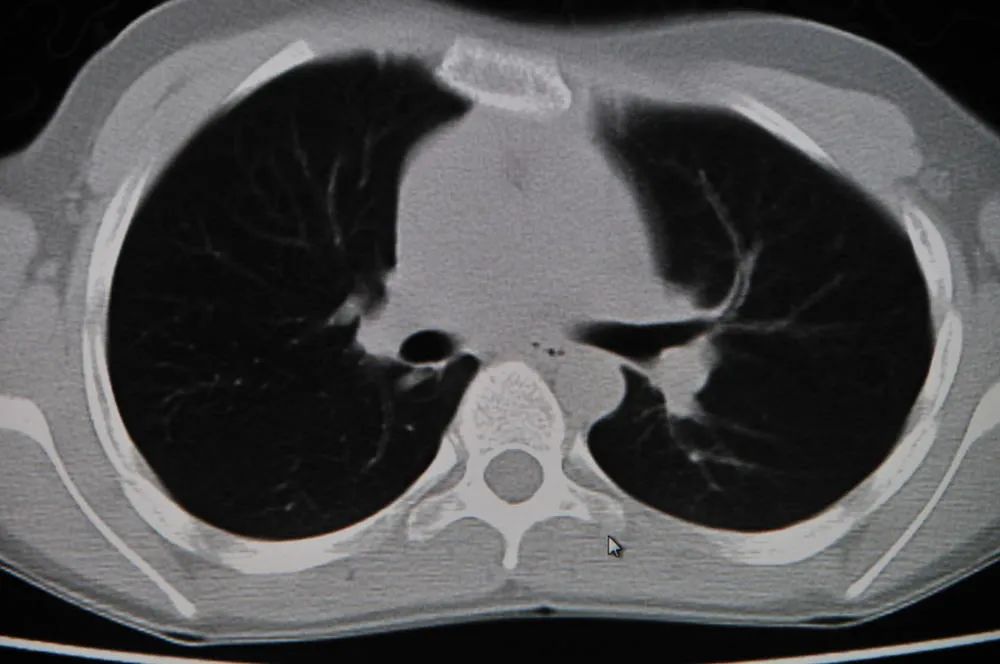

早期肺癌ct图影像

早期肺癌ct图

最近遇见几个早期肺癌,分享其ct特点,请多多指教!